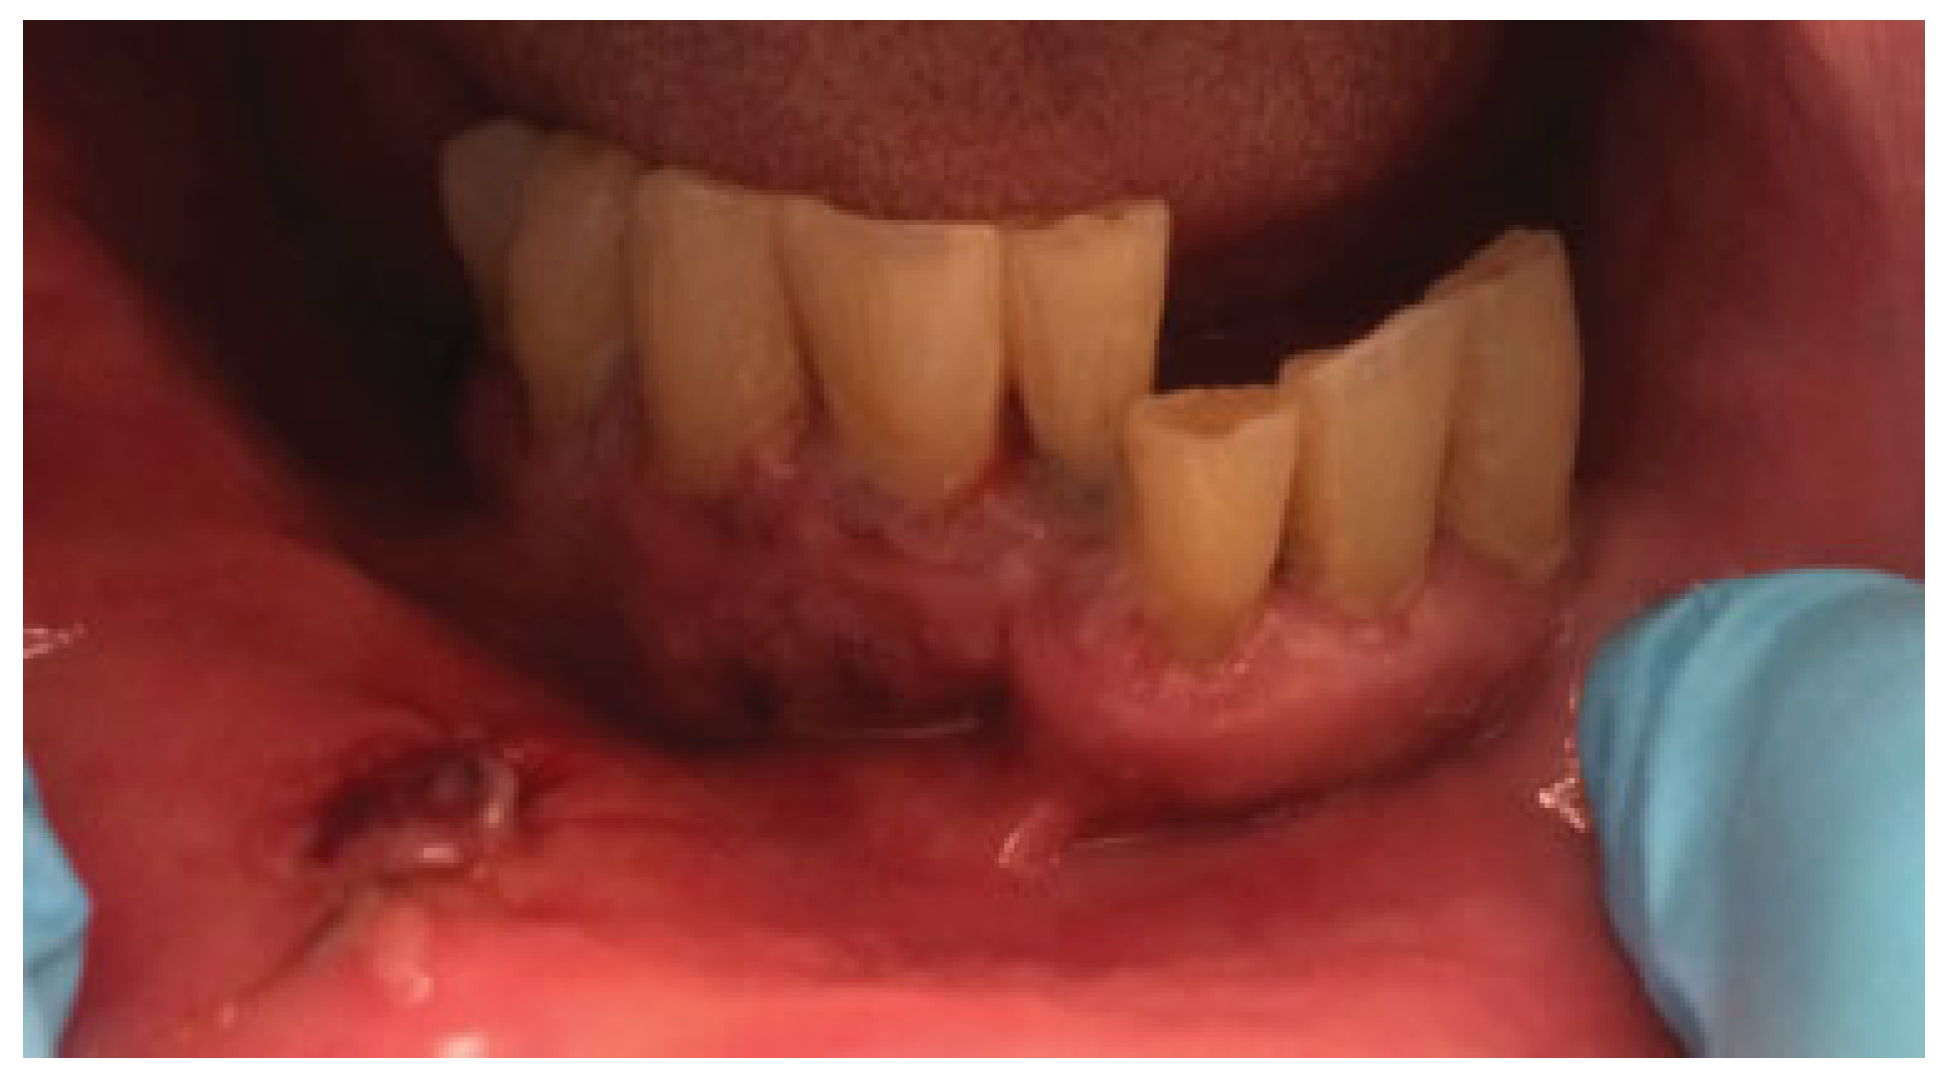

2.1. Case 1

2.2. Case 2